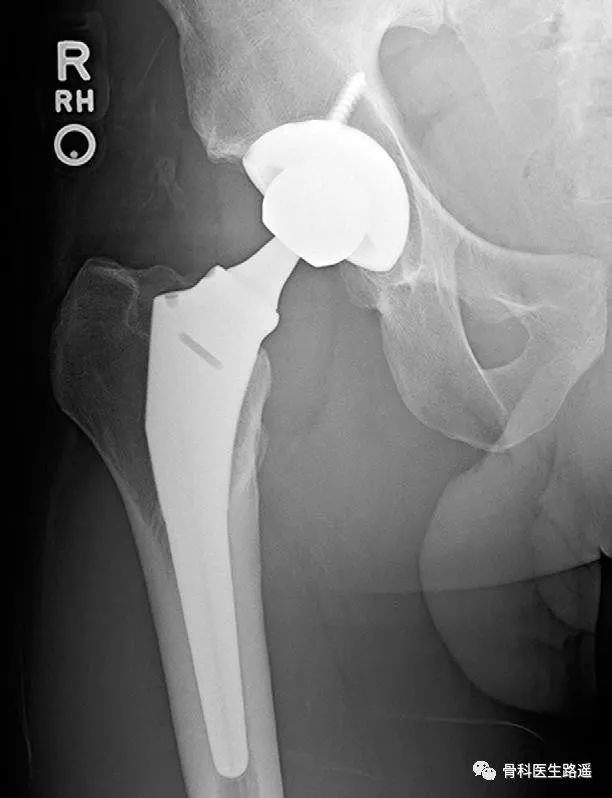

结果手术后6年来医院复查,男孩右侧手术部位假体整体情况非常好(如下图),左侧股骨头坏死区居然也没有什么变化。